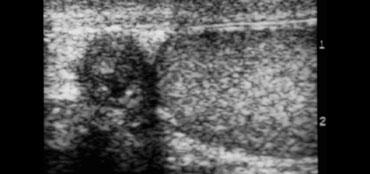

Ở bên trái là hai trường hợp nữa.

Ở ngoài cùng bên trái là một trẻ 10 tháng tuổi bị xoắn tinh hoàn.

Có nhiều lưu lượng máu trong các mô xung quanh tinh hoàn hơn so với trong tinh hoàn, điều này là bất thường, trừ khi trẻ bị viêm mô tế bào.

Ca bên cạnh là một trẻ lớn hơn.

Siêu âm thang xám cho thấy tinh hoàn bất thường.

Vì vậy đây có thể là xoắn tinh hoàn hoặc viêm tinh hoàn, nhưng sự vắng mặt của dòng chảy cho chúng ta biết rằng đây chắc chắn là xoắn tinh hoàn.